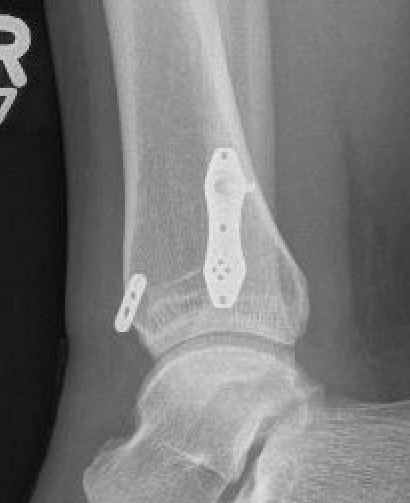

Screw fixation

Technique

AO surgery reference surgical technique

Open reduction of the distal tibio-fibular joint

Two screws

- level of syndesmosis (1.5 - 3 cm from joint)

- angle 30 degrees anterior

- 3 or 4 cortices

- 4 cortices probably more likely to break

- insert screws with ankle at neutral dorsiflexion

- consider removal at 4 - 6 months